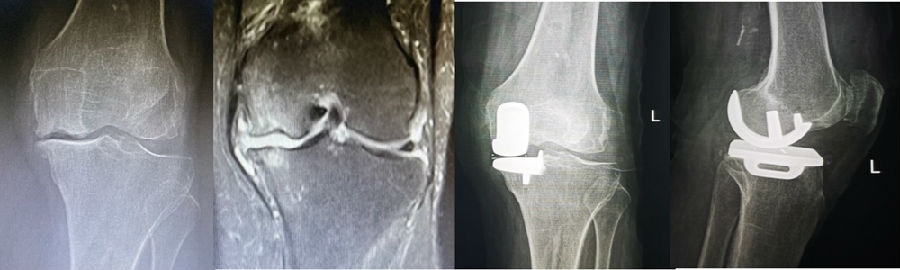

病例1:女,61岁,右膝关节诊断为Koshino Ⅲ期SONK,行右膝内侧单髁手术治疗。

(4)Koshino Ⅳ期SONK

由于存在继发退行性改变,一般不建议单纯行膝关节镜+自体骨软骨移植术。需在考虑5个因素的基础上兼顾患者年龄、性别和活跃程度,分别选择膝关节镜+HTO术+微骨折术、膝关节镜+HTO+坏死区病灶刮除+自体植骨术或单髁置换术。对于合并症状性髌股关节炎、外翻畸形、坏死区范围大影响单髁假体稳定性等的Koshino Ⅳ期膝关节股骨内侧髁SONK,采用全膝关节置换术。

病例2:女,81岁,行内侧单髁手术治疗,术后恢复良好。

综上,膝关节股骨内侧髁自发性骨坏死的阶梯治疗应遵循下图的治疗原则。